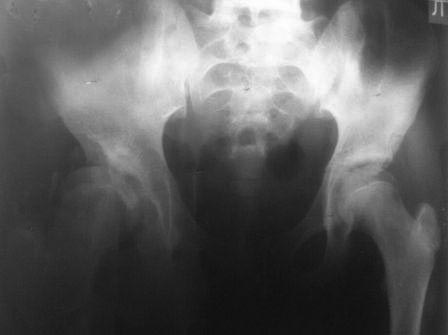

У нас реконструкция крыши делается по типу создание навеса (методика

УзНИИТО) в зависимости от недоразвития части крыши, ну чаще

передневерхней, сначала открываем сустав, ревизия, удаление

внутрисуставных тел, проверка хрящевой  губы, определение размера

недопокрытия головки,  дугообразная остеотомия крыши  по краю

прикрепления капсулы сустава к кости, параллельно стенки вертлужной

впадины до внутреннего кортикала , формируем крышу, после  устранение

торсии, вальгуса шейки и определяется размер укорочения, взятый

трансплантат внедряется в паз над крышей, примерно так.. То, что попало

в руки сейчас, примеры операции у пациентки 13лет, и результат у 12 лет,

до снимков не нашел, если найду еще отправлю.